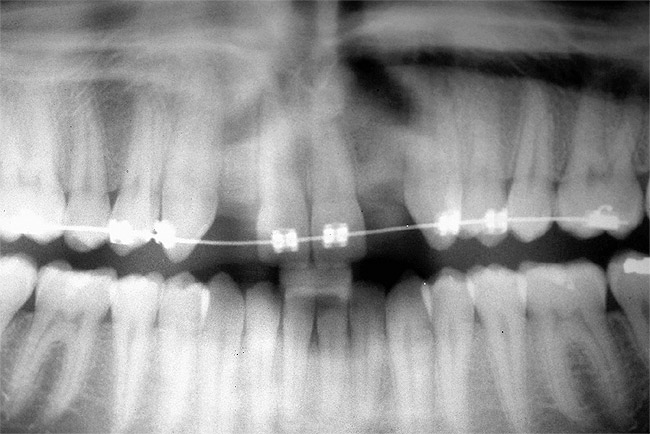

Periapical radiographs were taken to help determine the mesial-distal inclinations of the adjacent tooth roots (Figure 1). The radiographs revealed a serious issue, convergent roots for the right canine and right central, which eliminated that area as a potential implant-receptor site. The space between the left central and canine teeth was minimal, although the roots were relatively parallel. Clinical examination (manual palpation of the root eminences superiorly to the vestibule on the right side) confirmed the root convergence (Figure 2A). The flat, wide zone of the keratinized tissue and lack of interdental papilla was evident for the missing right lateral incisor. There was a marked difference in clinical appearance for the left lateral, which could impact the eventual plan of treatment (Figure 2B). Other significant clinical findings included bilateral facial bone concavities, which existed as a result of the congenitally missing tooth roots. As a diagnostic cue to the underlying bone topography, it is important to follow the demarcation between attached and unattached gingival tissue, and note the crestal width of the available keratinized tissue (Figure 2C).

Based upon the intraoral examination and periapical radiographs, additional orthodontic intervention was r.commended to move and rotate the roots to gain enough space for implant placement. This information was conveyed to both the parents and to the treating orthodontist. After several additional months, a panoramic radiograph was provided by the orthodontist to evaluate the distance between the clinical crowns and tooth roots (Figure 3). The lack of sharpness, definition, and radiographic artifacts made it impossible to determine whether implants could be successfully placed based on the 2D panoramic image. This diagnostic predicament was discussed with the patient and his parents, and it was suggested that a CT scan would be necessary to accurately assess the bone topography and spatial orientation of the adjacent roots. The parents agreed, and the patient was given a prescription for a CT scan study at a local radiology center.

Figure 3  After orthodontic therapy, the radiograph did not provide enough diagnostic information to determine if implants could be placed.

Figure 3